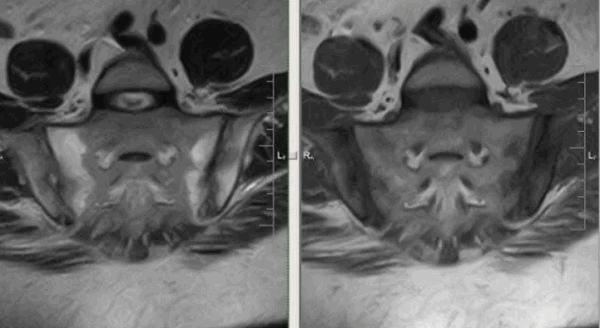

Для определения достоверного сакроилеита по МРТ необходимо наличие околосуставной зоны отека костного мозга одной анатомической области не менее, чем на двух последовательных срезах, или наличие зоны отека костного мозга двух и более анатомических областей хотя бы на одном срезе.

На рисунке - T2-Stir ВИ

Изменения выявляются в синовиальной (нижней и наружной) и в связочной (верхней и внутренней) частях сустава; в большей степени со стороны подвздошной кости.